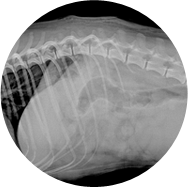

• 방사선 검사를 통한

정밀한 검사